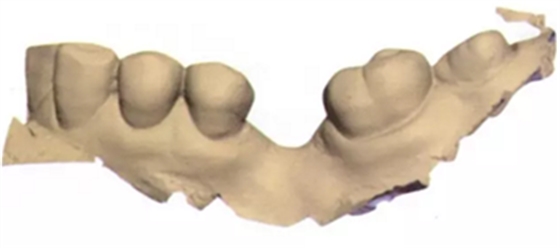

3b:無牙區(qū)的表面掃描

圖3c:表面掃描之后左側(cè)下頜骨區(qū)的重建圖

圖3d:在最大交錯(cuò)位數(shù)字化重建牙弓

在此次就診中,也用TRIOS掃描儀(3Shape;圖2與圖3b-d)掃描左側(cè)上下頜骨和上下牙弓并進(jìn)行咬合重建。只要把所有的診斷信息收集起來,第二天就可以復(fù)診治療。